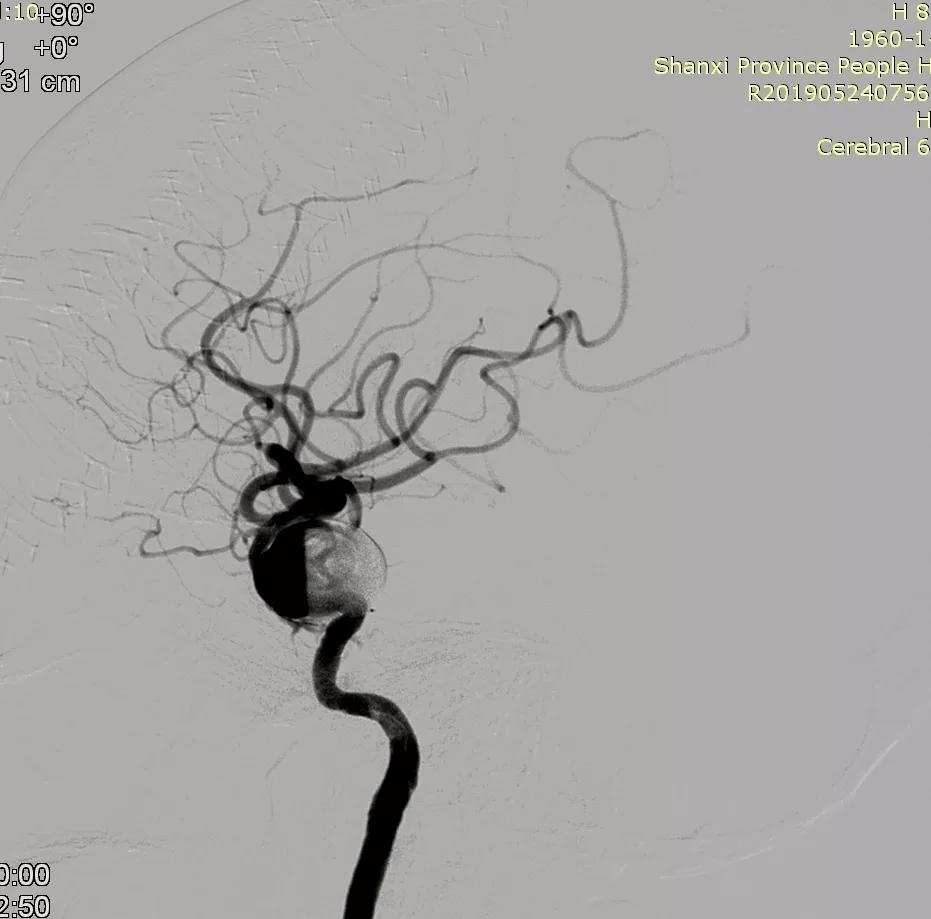

全脑血管造影可见左侧大脑中动脉动脉瘤,瘤体最大径:16.7mm,瘤颈宽:8.3mm。

Synchro 14微导丝导引支架导管,远端送入左侧中动脉下干远端困难,支架导管内穿行Tracxseed微导丝,双导丝导引支架导管顺利进入左侧中动脉下干远端,尾部链接Y阀1个,压力带1个。

经支架导管,置入Tubridge® 3.0×30mm,释放位置良好。

复查造影,动脉瘤造影剂明显滞留,各血管及分支通畅,流速正常。手术结束。